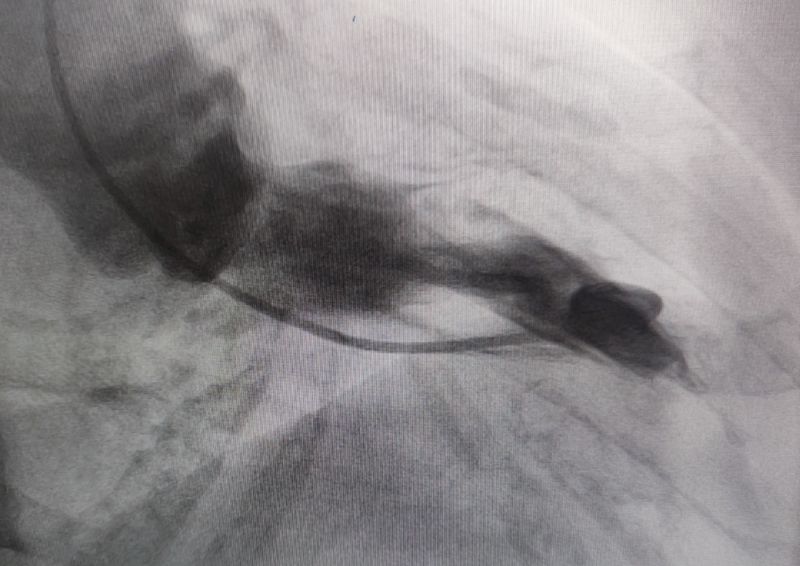

消融后造影

经过多轮严谨的术前讨论,在吴栋梁院长的专业指导下,崔旭辉主任医师团队决定在临时起搏器的安全保护下,为患者实施冠状动脉造影术及室间隔化学消融术。术中,团队通过造影精准锁定第一穿隔支为消融靶血管。测压数据显示:左室压260/15mmHg,流出道173/6mmHg,主动脉压106/70 mmHg,压力阶差达87mmHg。随后,团队使用2.0X15mm预扩球囊以8atm压力阻断第一穿隔支远端血流1分钟,再次测压时,压力从269/7mmHg骤降至174/4mmHg,这一结果充分证实该血管正是室间隔的有效供血血管。紧接着,团队通过SPRINTER OTW2.0×8mm球囊缓慢注入1.4ml无水酒精。10分钟后复测,左心室压降至136/5 mmHg,主动脉压为112/93 mmHg。术后第2天,王女士胸闷、气短、心悸等不适症状完全消失。复查心脏彩超显示:EF值与FS值保持稳定,收缩期左室流出道血流速度降至252cm/s,PG值为25mmHg。